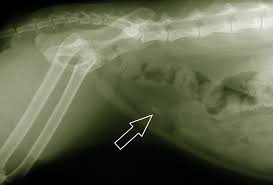

The best way to do this is to change the dog s diet. Kidney stones or kidney stone fragments can also pass through this system of tubes and into the ureter causing serious complications. However some breeds of dog are more susceptible to certain types of kidney stones than others.

Overview stones of the urinary tract begin as microscopic crystals that aggregate to form stones of variable size and shape anywhere within the urinary system including the kidneys ureters and urethra although stones of the urinary bladder are most common. Cystine stones excessive elimination of cystine in the urine is an inherited disorder of kidney tubular transport that is thought to be the primary cause of cystine stones figure 5. Follow up appointments for urinalysis and or abdominal x rays should be done every 4 6 weeks after treatment initiation to ensure stones are dissolving and new ones are not forming.

These techniques are helpful to provide the outline of the stones in your dog s kidney. Kidney stones in dogs happen when crystals or stones form in the kidneys usually due to an abnormal concentration of mineral salts in the urine. Dogs with small kidney stones really may show no signs at all.

Canine kidney stones diagnosis. Kidney stones may show up on x rays of the belly that are being taken for unrelated reasons as a so called incidental finding for instance they may be discovered when you think your pooch may have eaten something he shouldn t have like one of your favorite earrings. There are several types of bladder stones.